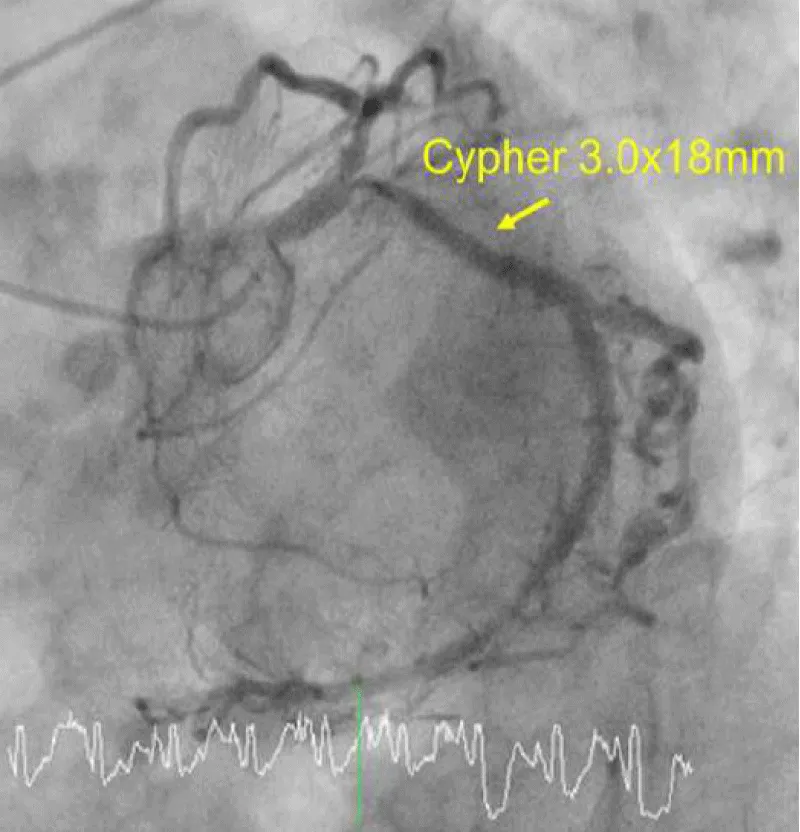

A 75-year-old woman presented with new-onset Canadian Cardiovascular Society Classification Class III angina. A coronary angiogram revealed a 90% blockage of the distal left main trunk (LMT) and a 99% blockage of the ostial left anterior descending coronary artery (LAD) (Video 1A) and (Video 1B). The Syntax Score, Society of Thoracic Surgeons (STS) score and left ventricular ejection fraction (LVEF) were 28, 1.65% and 74%, respectively. A 3.0 × 18-mm CYPHER™ stent had previously been implanted into the dominant proximal circumflex artery (LCx) in 2009 because of unstable angina (Figures 1A,1B). Although some persistent peri-stent contrast staining (PSS) was noted on an angiogram as early as June 8, 2015 (Figure 1C), a single treatment with clopidogrel for antiplatelet therapy was interrupted 7 days before an elective CABG. The patient started complaining of chest pain that corresponded with a marked ST elevation in the inferior posterior leads (Figure 2) and subsequently collapsed on August 7, 2016, in a general ward, 5 days after clopidogrel was discontinued. The patient had a history of dyslipidemia and hypertension but not diabetes, prior cerebrovascular accident, or chronic obstructive pulmonary disease. Her medication included clopidogrel (75 mg), rosuvastatin (2.5 mg), nicorandil (15 mg) and benidipine (8 mg) daily. An emergent bedside echocardiogram showed posteroinferior hypokinesia without any dissection flap in the aortic root (Video 2). Following an aggressive cardiopulmonary resuscitation (CPR) in the general ward, femorofemoral venoarterial extracorporeal membrane oxygenation (VA-ECMO) was inserted in a catheterization laboratory (Video 3). An emergent angiogram revealed a thrombotic stent occlusion of the proximal LCx (Video 4A) and (Video 4B). During angiography, the patient remained pulseless and suffered repeated bouts of ventricular fibrillation, which necessitated defibrillations. When manual aspiration thrombectomy was performed, adequate coronary flow returned instantaneously (Video 5) and (Video 6) and systolic blood pressure improved to 90 mmHg. In the end, an intra-aortic balloon pump was placed and ECMO could be tapered off the same day. The maximum creatine phosphokinase and creatine kinase-MB levels were 4398 and 269 IU/mL, respectively. The following day, the patient underwent on-pump CABG with left internal thoracic artery-LAD and saphenous vein graft-obtuse marginal anastomoses. The patient survived and recovered well without any neurological defect. As of today, LVEF is 55% and single clopidogrel therapy is ongoing. Both bypass grafts and the stent were patent (Video 7).

Figure 1B: A 3.0 × 18-mm CYPHER™ stent was placed without any complications such as a stent-induced dissection.